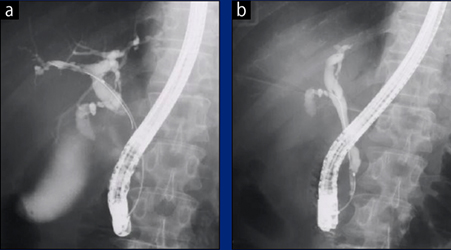

症例2:Cアームにより体位変換不要で角度付けが行え,分離ができたB3/B4a

a:B3/B4aが重なっており,識別が困難

b:Cアームによる角度付けでB3/B4aの識別が可能

症例3:octave SPにより,線量を低減しながら高精細な画像を撮像可能。PSCの胆管粘膜上皮の炎症や狭窄をより詳細に観察可能であった。

a:肝門部の胆管充溢像

b:下部胆管での胆管充溢像

ともに末梢胆管の狭窄や胆管粘膜の炎症所見が観察できる。